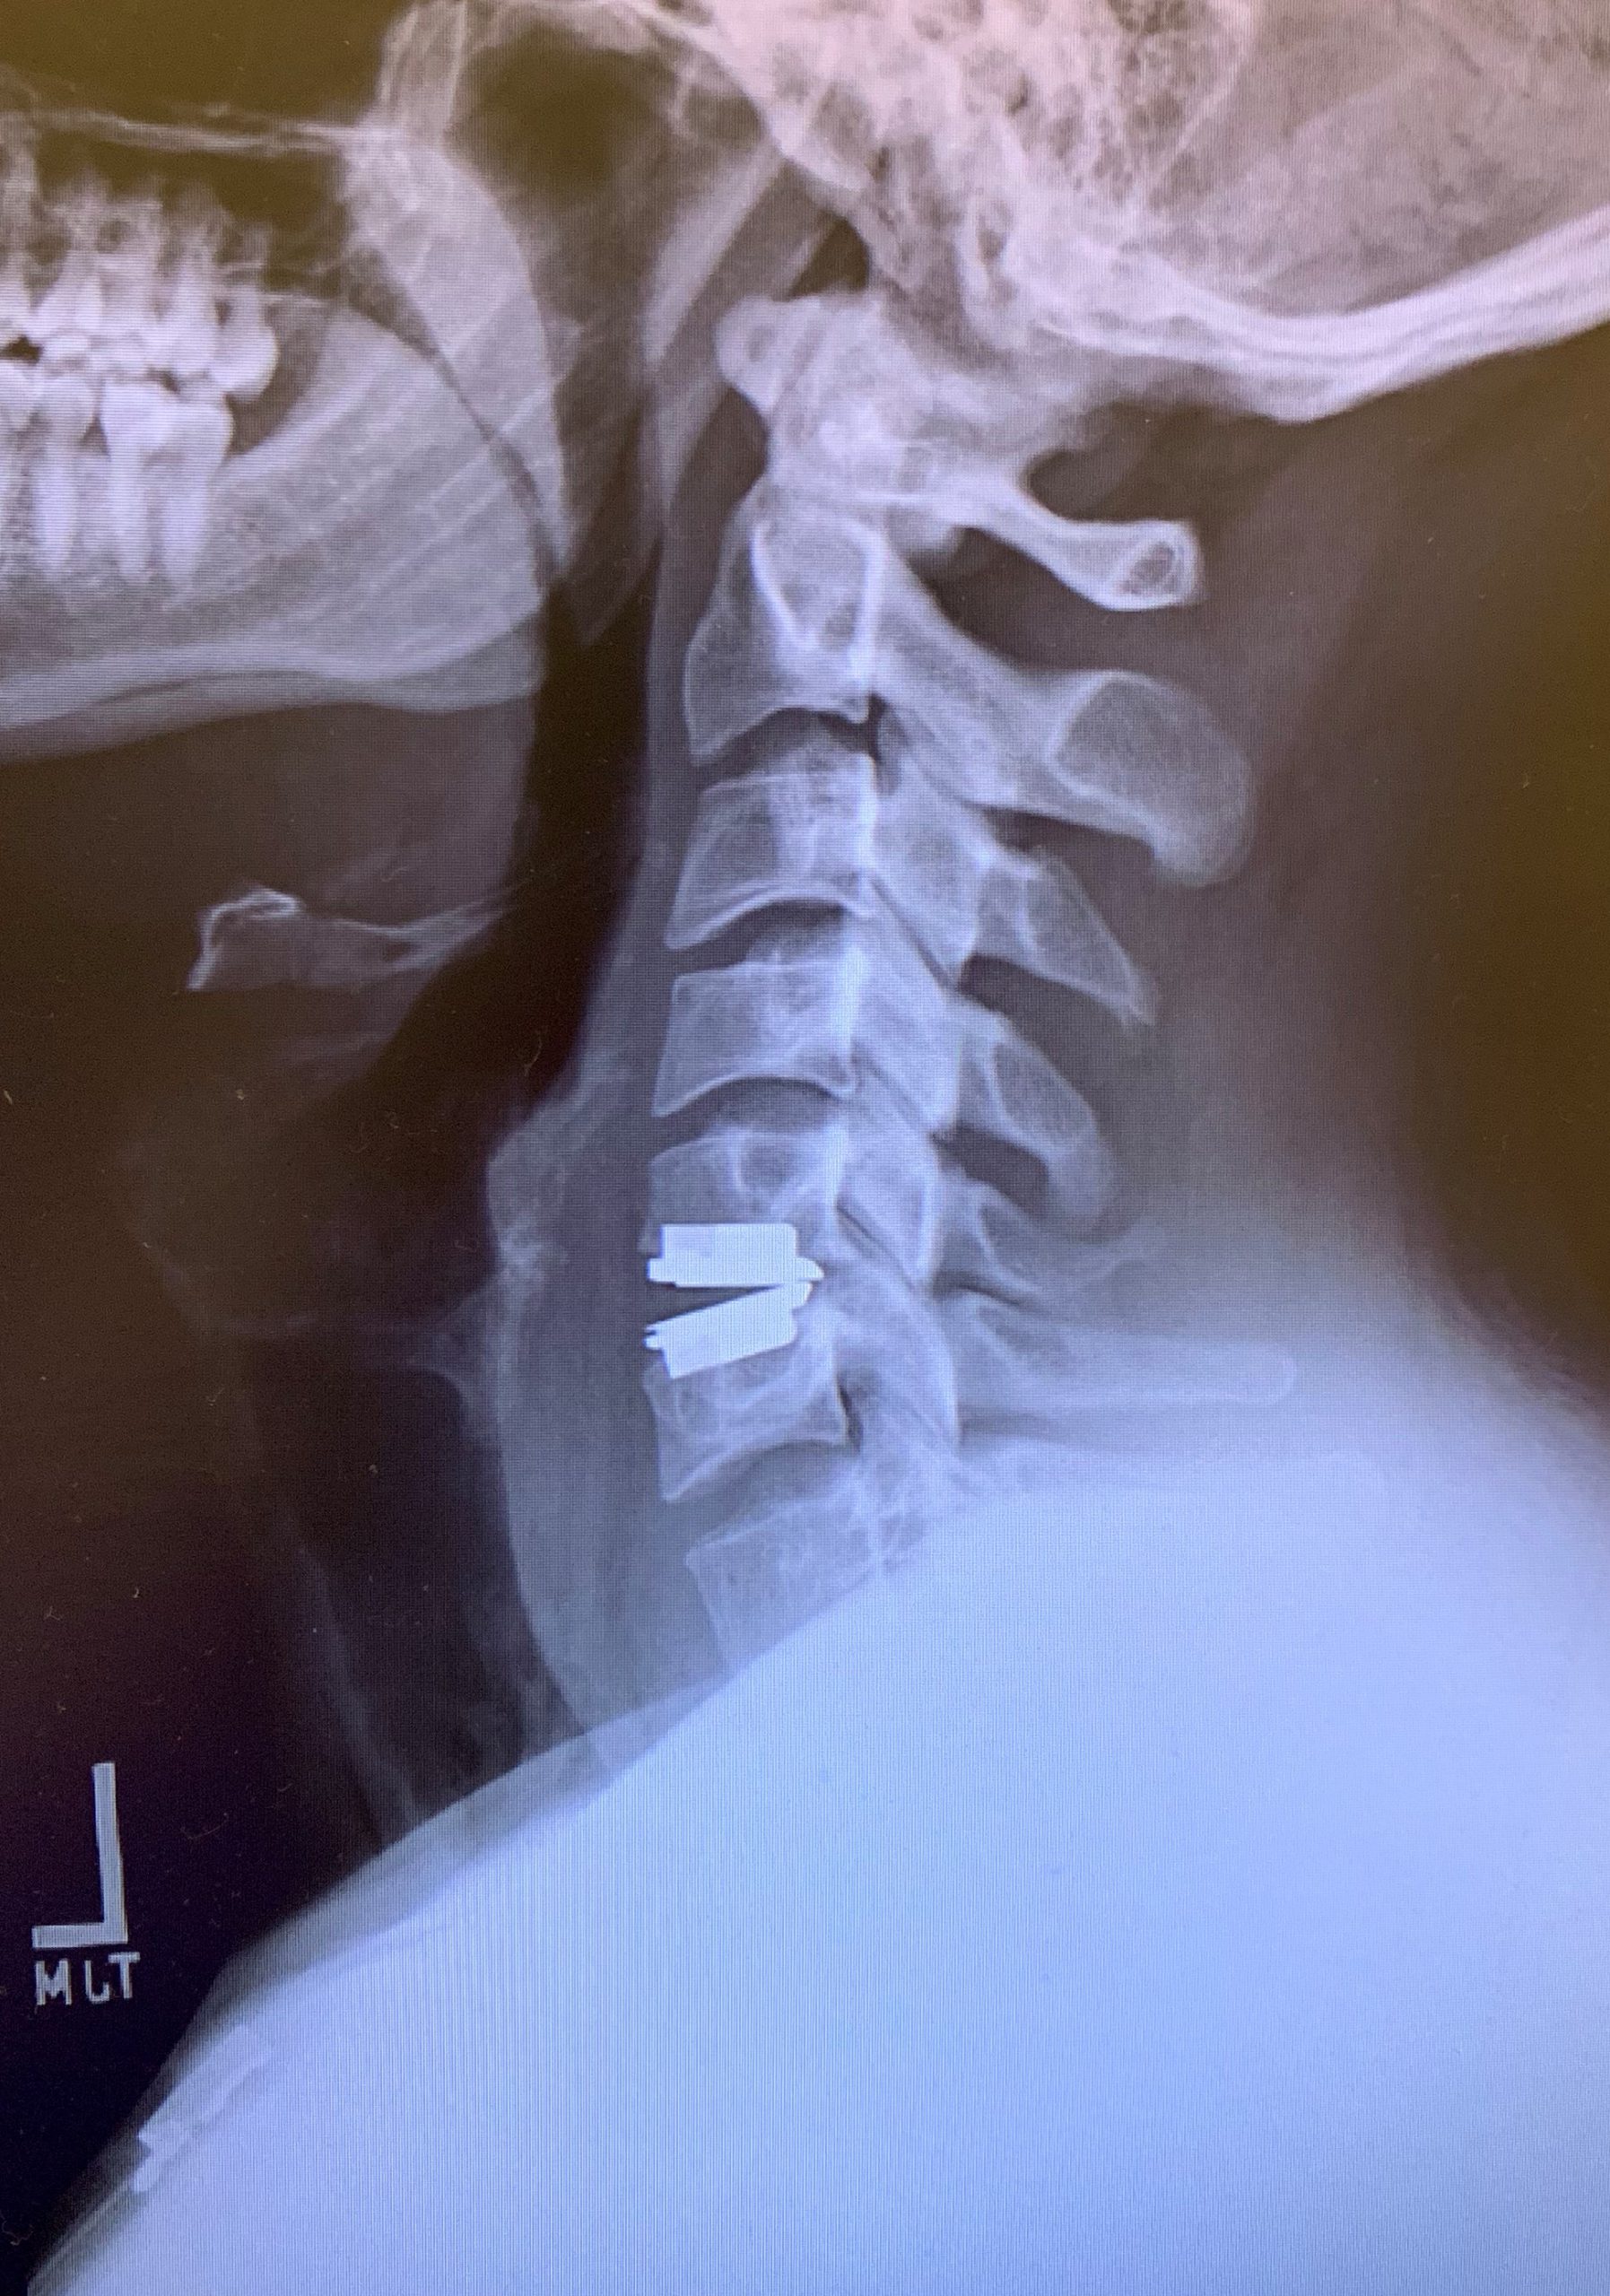

Patient underwent C5/6 Artificial Disc Replacement and was discharged the next morning.

Post-operatively he has been doing excellent with complete resolution of symptoms, and was so grateful that he decided to spoil the office staff!